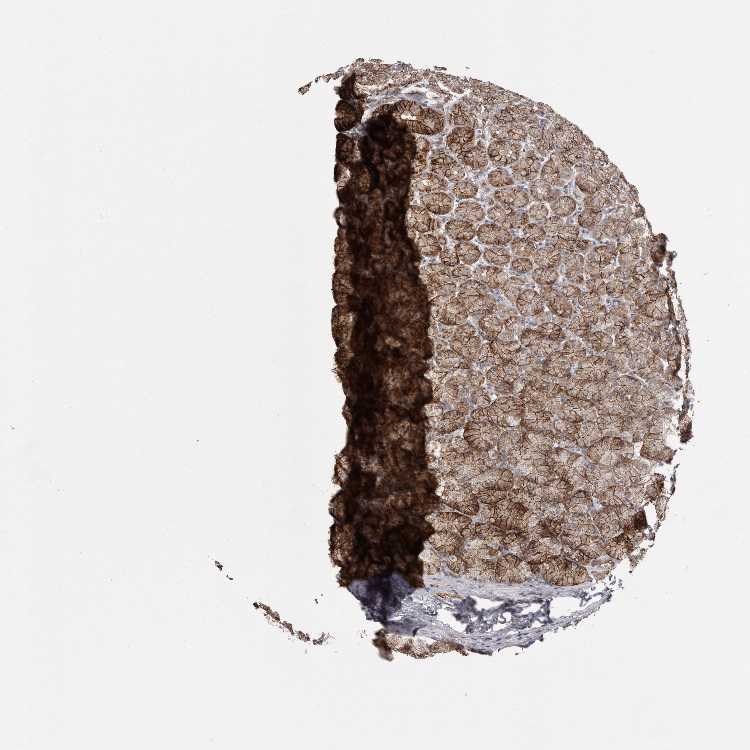

STOMACH 1 - Antibody stainingi

Antibody staining in the annotated cell types in the current human tissue is reported as not detected, low, medium, or high, based on conventional immunohistochemistry profiling in selected tissues. This score is based on the combination of the staining intensity and fraction of stained cells.

Each image is clickable and will lead to virtual microscopy that enables deeper exploration of all samples and also displays staining intensity scores, fraction scores and subcellular localization as well as patient and tissue information for each sample.

Antibody HPA023871Antibody HPA052645

Glandular cells HighHigh